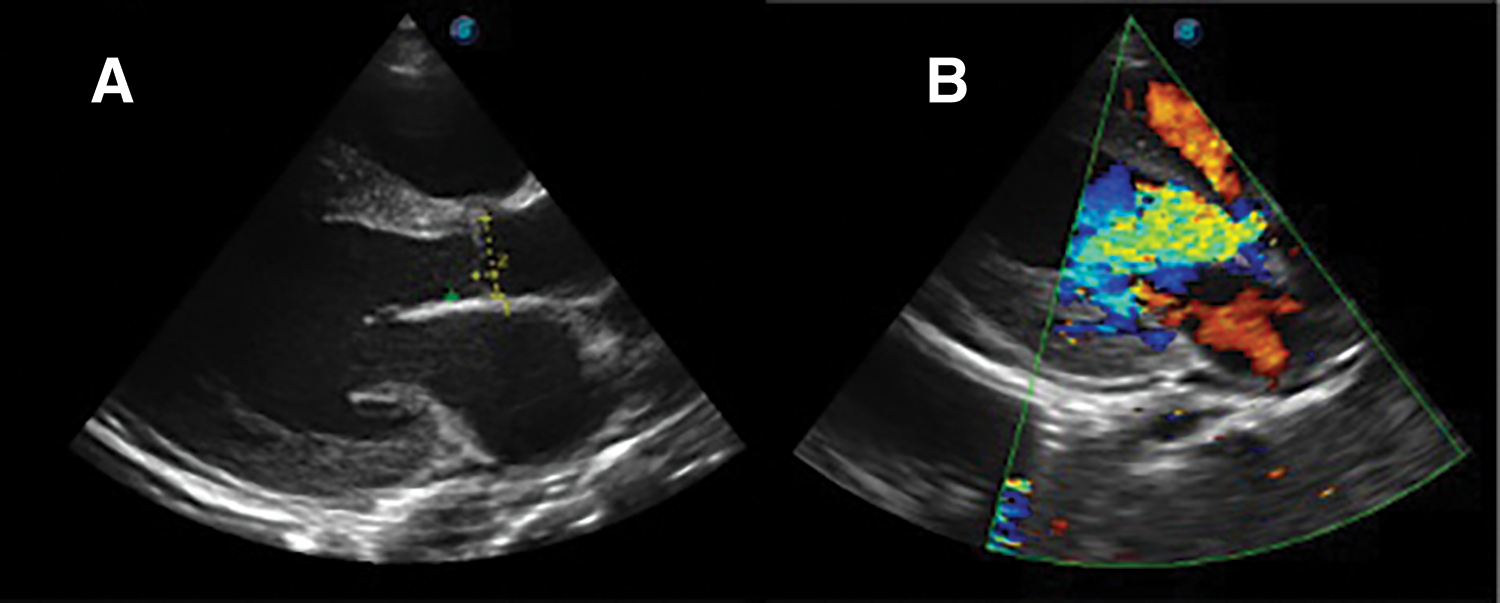

Further review and meticulous physical examination and investigations revealed confused and restless patient, febrile (T = 40°C), pale, acyanosed, RR: 38 breaths/min, SPO2 90%, pulse rate 122/min, blood pressure of 120/40 mmHg, Jugular venous pressure not raised, displaced apex and hyperdynamic, heart sound: S1, S2 and S3 gallop, PSM grade 3/6 loudest at 4th left intercostals space lateral to sternal border, tricuspid PSM grade 1/6 epigastrium, aortic diastolic murmur grade 2/4, bi-basal fine crackles. a provisional diagnosis of congenital heart disease (VSD) with aortic incompetence complicated by infective endocarditis, sepsis, AKI and acute left ventricular HF was entertained with differential diagnosis of Rheumatic heart disease (RHD) with complications. He was started on oxygen therapy and switched from generic ceftriaxone to the branded ceftriaxone (Rocephin). Metronidazole was stopped and gentamicin added adjusted for renal function, he also received furosemide along with conservative renal therapy and close monitoring. Additional relevant investigations were requested which include (1) Laboratory test as indicated in (Table 1b) (2) Electrocardiogram (ECG) which showed sinus tachycardia with heart rate of 115 beat per min (Fig. 1). (3) Chest X-ray (CXR): Showed cardiomegaly of biventricular configuration with cardiothoracic ratio of 0.61, prominent pulmonary vasculature, upward blood diversion and blunted left costophrenic angle (Fig. 2). (4) Transthoracic echocardiography (TTE): revealed interventricular septal thickness of 9.4 mm and left ventricular posterior wall thickness of 13.5 mm. Moderately dilated left ventricle (LV) with internal diameter of 66.4 mm, mildly dilated left atrial with internal of diameter 44.1 mm, mildly dilated right ventricle with internal diameter of 43.9 mm, moderately dilated right atrium with internal diameter of 53.2 mm, Peri-membranous VSD measured 5.3 mm in size with color Doppler demonstrating left to right shunt (Fig. 3A,B). Aortic valve prolapse of the non-coronary cusp 4.5 mm from the plane and severe aortic regurgitation [Width of vena contracta of 7.4 mm and regurgitant jet width/LV out flow tract diameter ratio of 2.1 cm/2.6 cm of 0.80 (80%)] (Fig. 4A,B), large oscillating echogenic mass attached to tricuspid valve leaflet was noted (Fig. 5) and (Supplementary Materials Video S1). LV Ejection fraction (EF) was 64.7% on M-mode guided 2-D with fractional shortening of 36.3% and normal RV systolic function (TAPSE: 20.4 mm). LV end-diastolic volume index was 135.8 mL/m2 (Severely abnormal), while LV end-systolic volume index was 47.9 mL/m2 (Severely abnormal) and LV mass index (LVMI) was 209.3 g/m2 (Severely abnormal). Other heart valves appeared normal in motion and morphology. Moderate mitral regurgitation, severe tricuspid regurgitation and mild pulmonary regurgitation were noted. Pulmonary arterial systolic pressure at rest was 52.2 mmHg.

Figure 4: TTE parasternal long axis view, (A): showing aortic valve prolapse of non-coronary cusp and (B): color doppler demonstrating aortic regurgitation